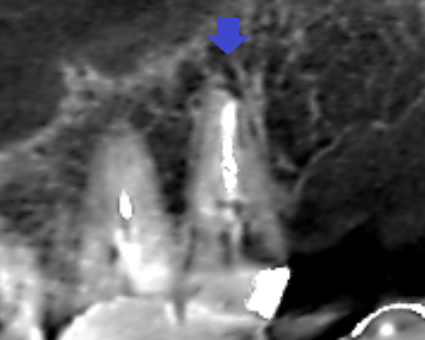

精密根管治療6カ月後の経過観察時の矢状断のCT画像です。上顎第二大臼歯の口蓋根の先にみられた膿の影が縮小し歯槽骨が再生しています。